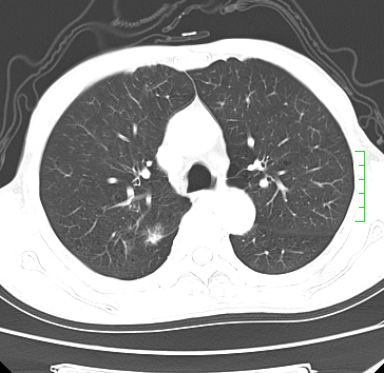

m,73y。膝关节疼痛伴双下肢水肿。入院常规胸片发现结节灶。增强为静脉期。

浅分叶、棘突,考虑右下肺周围型肺癌

考虑周围型肺癌  ,双上肺结核。

肿块周围可见局限性气肿,考虑肺癌可能性大。双肺上叶继发型肺结核。

指套征,强化明显,近侧肺组织局限性肺气肿,考虑支气管类癌,慢支、肺气肿、双上陈旧性tb、冠脉钙化。

鉴别:先天性支气管闭锁,变态反应性支气管肺曲霉菌病,肺癌,支气管囊肿,支扩黏液嵌塞。

1)考虑右肺下叶周围型肺癌。2)右肺上叶及左肺感染性病变(结核可能)。3)肺气肿。4)冠状动脉钙化。